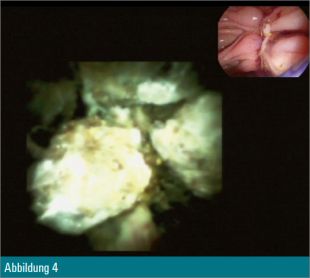

Eine 55-jährige Patientin wurde wegen eines Tonnenkonkrements im Ductus choledochus zur ERCP vorstellig (Abbildung 1). Nach Papillotomie erfolgte zusätzlich eine Ballondilatation der Papille auf 12 mm. Anschließend wurde mit dem Cholangioskop in den Ductus choledochus eingegangen (Abbildung 2) und eine elektrohydraulische Zertrümmerung des Konkrements unternommen (Abbildung 3).